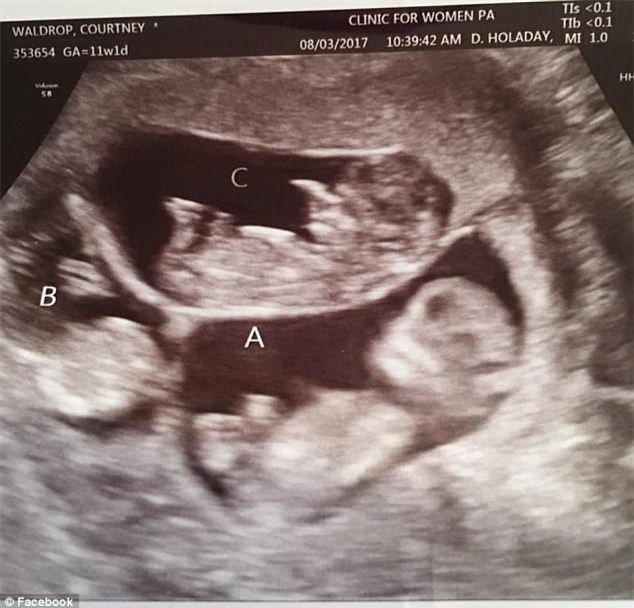

Trong lần siêu âm vào tháng 6, các bác sĩ đã nghe được nhịp tim của 6 bé trong tử cung người mẹ. Đây là điều vừa đáng mừng, vừa đáng lo ngại bởi các nhân viên y tế rất lo là 6 bé sẽ chào đời sớm.

Hình ảnh siêu âm của chị Courtney. (Ảnh: dailymail)